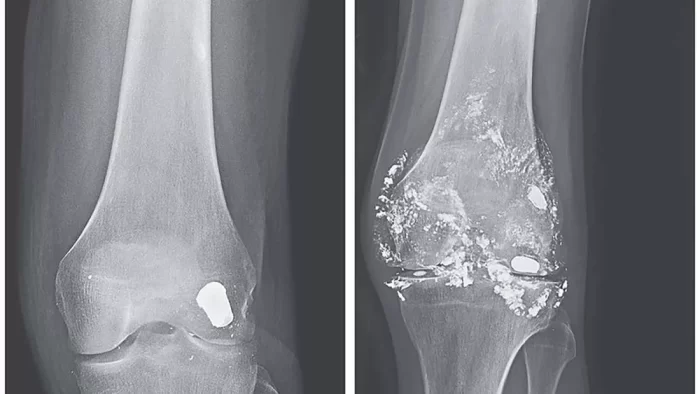

Esta pesquisa utilizou trinta ratos Wistar expostos a solução de acetato de chumbo (3 g/L) ao longo de 90 dias. Estes animais foram divididos em três grupos distintos de 10 cada. O grupo C (BioFAO) recebeu uma ultradiluição equivalente (preparação FAO 155CH), administrada de forma oral. Foram acompanhados ganho de peso, comportamento, marcadores bioquímicos e níveis de Pb em ossos e rins. Amostras foram enviadas ao CEATOX/UNESP para quantificação.

O BioFAO Chumbo favoreceu eliminação ósteo-tecidual de Pb em período muito inferior à meia-vida natural (27 anos), sem alterações patológicas detectáveis.

A pesquisa demonstrou que o medicamento BioFAO Chumbo, uma ultradiluição sem presença molecular detectável, não apresenta toxicidade e atua de modo oposto ao chumbo químico: promoveu eliminação acelerada do metal dos tecidose restauração de parâmetros hepáticos e renais. Houve redução de 95 % do chumbo ósseo (p < 0,05), fenômeno compatível com ação informacional e ressonante, e não farmacodinâmica material.